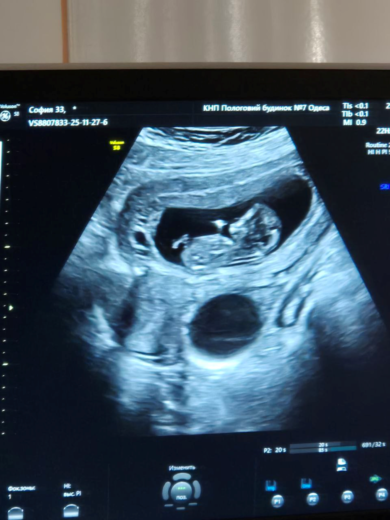

Poikamme on ollut erityinen siunaus: hän puhuu yhä enemmän, rukoilee itse ja jopa toistaa rukouksiamme. Jumala on antanut meille uskomattoman lahjan – odotamme toista lasta! Ultraäänitutkimus osoittaa, että vauva kehittyy hyvin ja sydän lyö normaalisti. Olemme tästä ihmeestä hyvin kiitollisia Jumalalle.